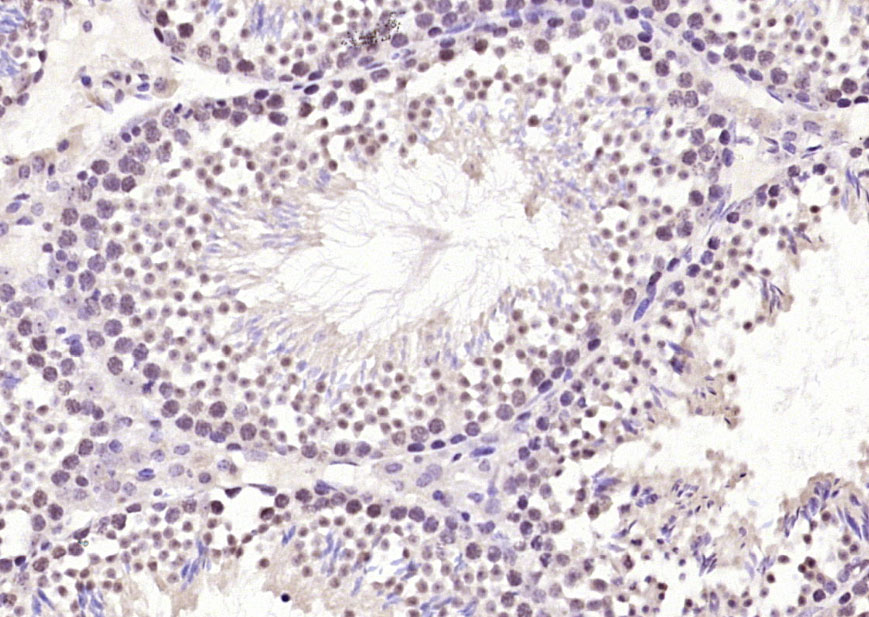

Paraformaldehyde-fixed, paraffin embedded (mouse testis); Antigen retrieval by boiling in sodium citrate buffer (pH6.0) for 15min; Block endogenous peroxidase by 3% hydrogen peroxide for 20 minutes; Blocking buffer (normal goat serum) at 37°C for 30min; Antibody incubation with (Ube2N) Polyclonal Antibody, Unconjugated (bs-8351R) at 1:200 overnight at 4°C, followed by operating according to SP Kit(Rabbit) (sp-0023) instructionsand DAB staining.